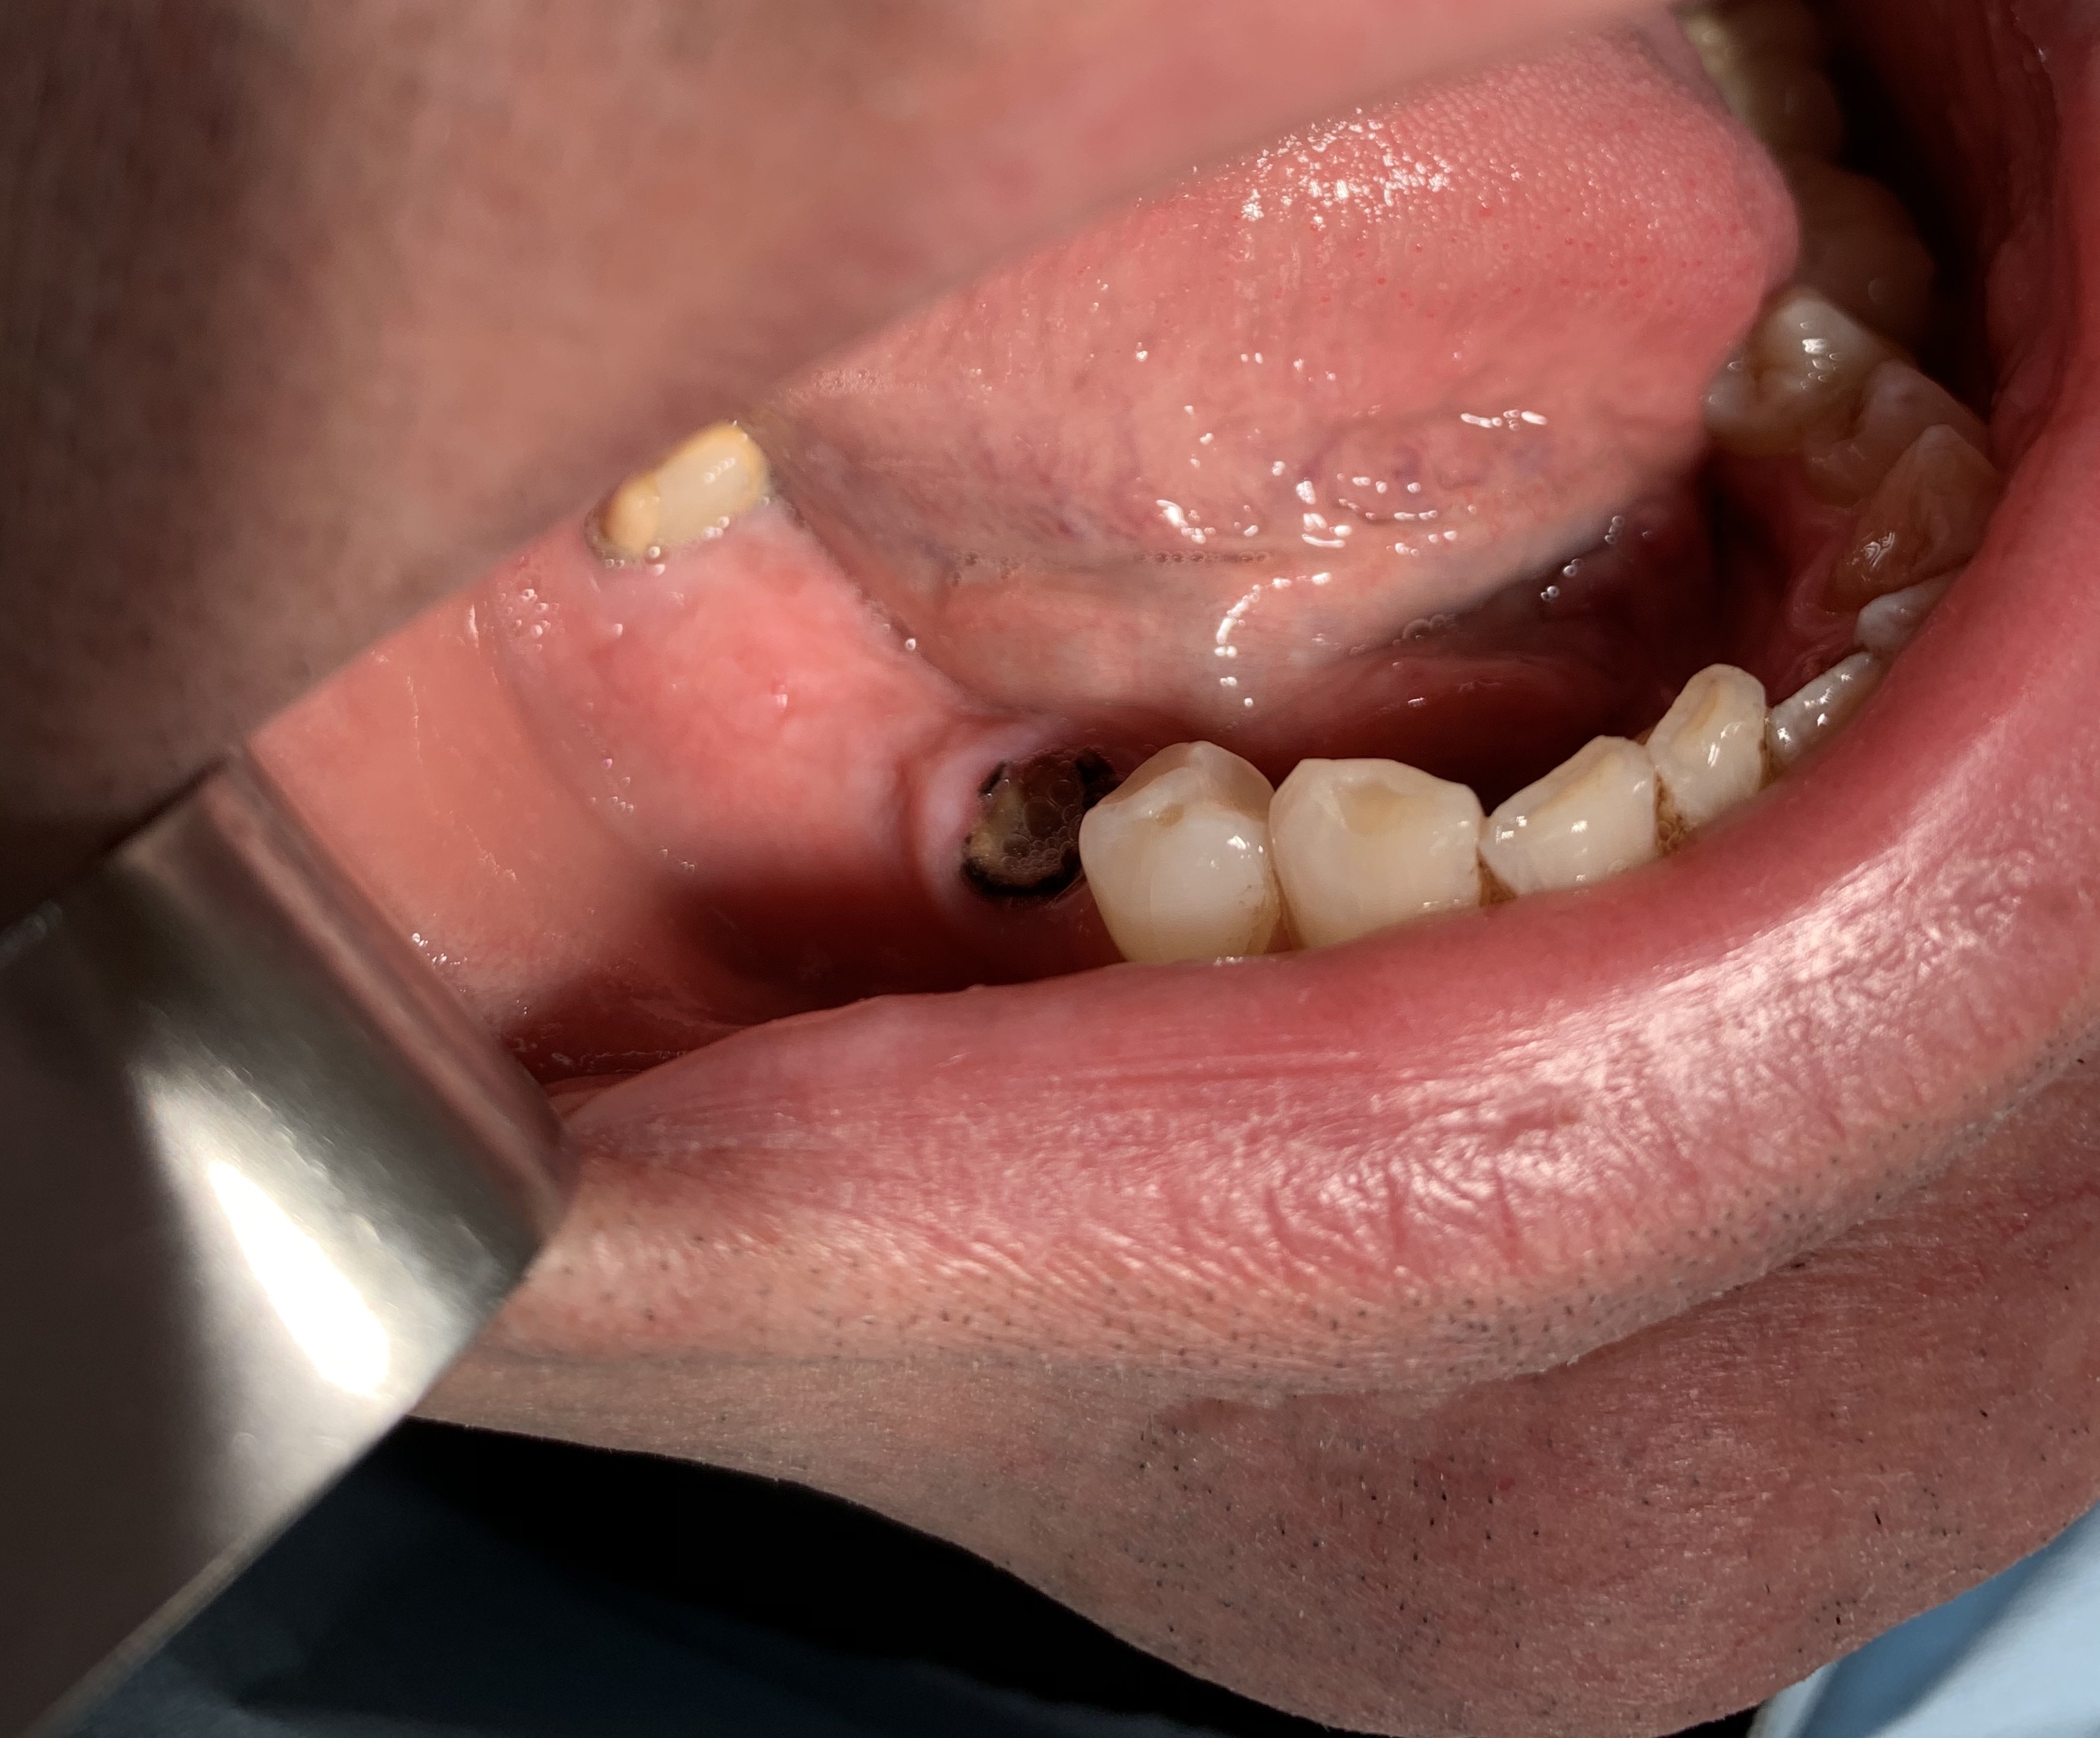

1 - AN INCISIVE CASE

Fracture of lower incisor element 31 and implant rehabilitation